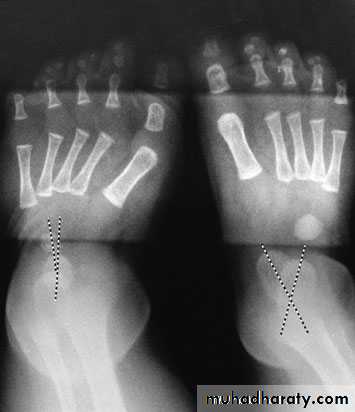

X-ray:

Lines can be drawnthrough the long axis of the talus parallel to its medial border & aline passing in the longtudinal axis of calcanium parallel to its latral border should de 20-40 digree